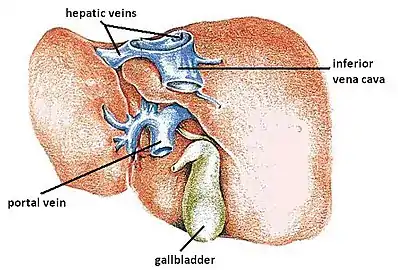

The liver is connected to two large blood vessels: the hepatic artery and the portal vein. The hepatic artery carries oxygen-rich blood from the aorta via the celiac trunk, whereas the portal vein carries blood rich in digested nutrients from the entire gastrointestinal tract and also from the spleen and pancreas.[8] These blood vessels subdivide into small capillaries known as liver sinusoids, which then lead to hepatic lobules.

Blood supply

The liver receives a dual blood supply from the hepatic portal vein and hepatic arteries. The hepatic portal vein delivers around 75% of the liver's blood supply and carries venous blood drained from the spleen, gastrointestinal tract, and its associated organs. The hepatic arteries supply arterial blood to the liver, accounting for the remaining quarter of its blood flow. Oxygen is provided from both sources; about half of the liver's oxygen demand is met by the hepatic portal vein, and half is met by the hepatic arteries.[40] The hepatic artery also has both alpha- and beta-adrenergic receptors; therefore, flow through the artery is controlled, in part, by the splanchnic nerves of the autonomic nervous system.

Blood flows through the liver sinusoids and empties into the central vein of each lobule. The central veins coalesce into hepatic veins, which leave the liver and drain into the inferior vena cava.[41]

The liver and its veins

The liver and its veins Diagram of liver, lobule, and portal tract and their inter-relations

The central area or hepatic hilum, includes the opening known as the porta hepatis which carries the common bile duct and common hepatic artery, and the opening for the portal vein. The duct, vein, and artery divide into left and right branches, and the areas of the liver supplied by these branches constitute the functional left and right lobes. The functional lobes are separated by the imaginary plane, Cantlie's line, joining the gallbladder fossa to the inferior vena cava. The plane separates the liver into the true right and left lobes. The middle hepatic vein also demarcates the true right and left lobes. The right lobe is further divided into an anterior and posterior segment by the right hepatic vein. The left lobe is divided into the medial and lateral segments by the left hepatic vein.